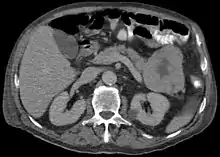

Light microscopy of an acinar cell carcinoma biopsy typically shows granular appearance.[6] Immunohistochemistry is usually positive for trypsin, chymotrypsin and lipase.[6] On genetic testing, altered genes/proteins are typically found for p53, SMAD4, APC, ARID1A and GNAS.[6]